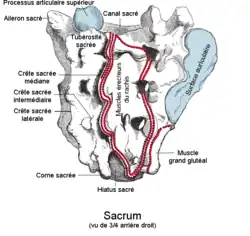

Face dorsale

La face dorsale postérieure est convexe et sous-cutanée.

Elle est divisée en son milieu par la crête sacrale médiane hérissée de trois à quatre tubercules : les tubercules sacrés postéro-internes. Elle est le résultat de la fusion des processus épineux des vertèbres sacrées. Elle bifurque au niveau du quatrième foramen sacré postérieur (quelquefois au niveau du troisième) par une bifurcation qui forme le hiatus sacré limitant l'ouverture inférieure du canal sacral. Les branches de la bifurcation forment les cornes sacrales.

De chaque côté de cette crête, la fusion des lames des vertèbres sacrées, forme les gouttières sacrées.

Latéralement aux gouttières, la fusion des processus articulaires laisse deux crêtes indistinctes les crêtes sacrales médiales.

Latéralement se trouvent quatre perforations ovalaires les foramens sacrés postérieurs.Ils diminuent de taille de haut en bas et sont plus petits que les foramens sacrés antérieurs avec lesquels ils communiquent. Ils laissent le passage pour les racines postérieures des nerfs sacrés.

À l'extérieur des foramens, la fusion des apophyses transverses des vertèbres sacrées forme une crête sacrale latérale formées par les tubercules sacrés postéro-externes (ou tubercules conjugués)

Les quatre tubercules supérieurs transversaux sont des points d'insertion pour la partie horizontale des ligaments sacro-iliaques postérieurs. Les tubercules de la troisième vertèbre sont des points d'insertion pour les faisceaux obliques des ligaments sacro-iliaques postérieurs et ceux des quatrième et cinquième vertèbres sont des points d'insertion pour les ligaments sacro-tubéraux.

Canal sacral

Le canal sacral est le conduit osseux dans le sacrum qui est dans la continuité du canal vertébral.

Il a la forme d'un prisme triangulaire se rétrécissant vers le bas, qui suit la courbure à concavité antéro-inférieure du sacrum.

Il débute à la base du sacrum par une ouverture entre la surface articulaire médiale et la crête sacrale médiane. Il se termine en bas au niveau du hiatus sacré.

Il donne naissance latéralement à quatre foramens intervertébraux, qui bifurquent pour s’ouvrir sur les faces antérieure et postérieure par les foramens sacrés antérieurs et postérieurs.